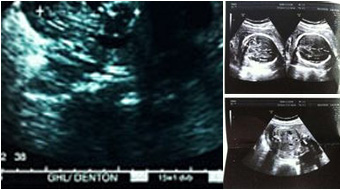

四维彩超不再是仅仅感觉宝宝的呼吸和运动,而是可以亲眼目睹他们的一举一动和乖巧的秀容。更为重要的是,四维彩超能够多方位、多角度地观察宫内胎儿的生长发育情况,为早期诊断胎儿先天性体表畸形和先天性心脏疾病提供准确的科学依据。

四维彩超检查的较佳时间是22-26周,在这段时期检查,因为胎儿较小,羊水较多,胎儿活动度大,体表也比较丰满,宫内拍摄效果较佳,有利于胎儿四维超声成像和胎儿畸形筛查,是排畸的较好时期,准妈妈们千万不要错过。

排畸:范围更广,准确率高

美国GE-E8四维彩超的检查范围广,增加了颅骨内透明隔腔、小脑蚓部、鼻骨、双侧耳廓;心脏内;双侧上臂及其内肱骨等部分的检查评估,灵敏度和诊断结果参考性高。 -

全面:360°立体展示,检查更全面

可以360°立体展示胎儿各器官的发育情况,对胎儿解剖结构、健康发育状况的检查更为详细。为早期筛查各种胎儿先天性畸形和先天性心脏疾病等提供全面准确的影像依据。 -

产前排畸超声诊断中无可取代

可准确提供有关胎儿的大小、羊水多少、脐带是否绕颈等信息;并且检测胎儿先天性缺陷的准确度更高,降低误诊漏诊现象,在产前排畸检查的超声图像诊断中无可取代。